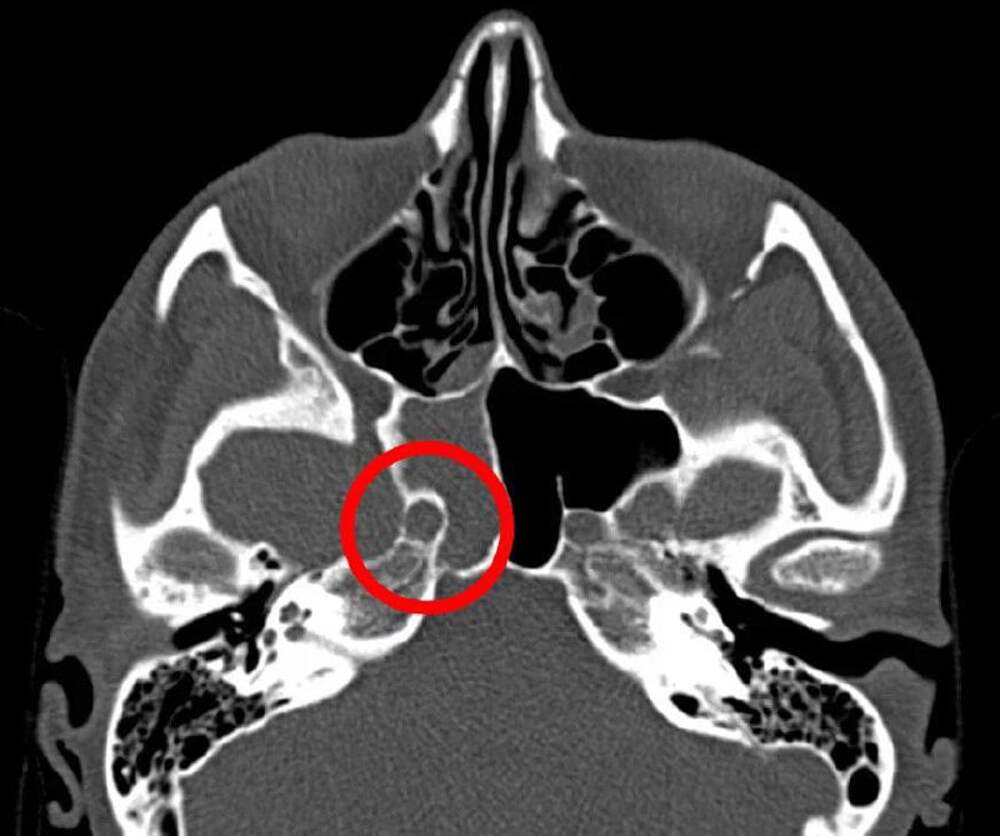

Из-за синегнойной палочки В Нижнем Новгороде мужчина временно потерял слух после купания в официально разрешённой зоне на реке, сообщает ИА «Стационар-Пресс». После купания у него началась сильная лихорадка, опухло лицо и появилась острая боль в ухе. Врачи диагностировали